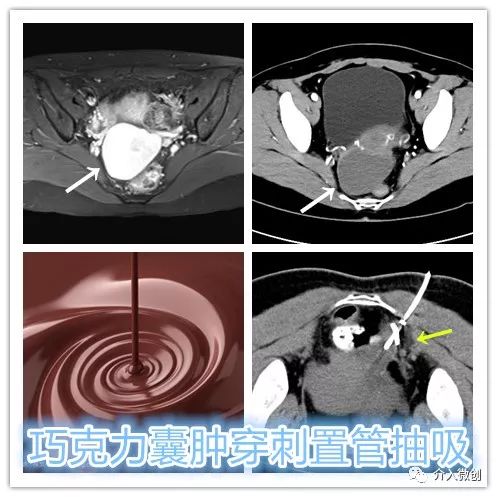

CT引导下巧克力囊肿穿刺置管抽吸+硬化治疗

经留置引流管抽吸出浓稠积血,使用生理盐水反复冲洗直至囊液转为清亮,随后注入聚桂醇硬化剂保留腔内硬化破坏囊壁,2天后拔除引流管。